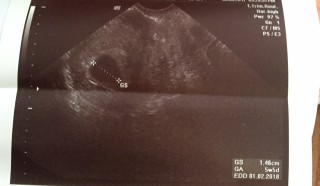

写真:5w5d:ゆーちゃんさん

胎嚢は約1cmで順調に育っていて、卵黄嚢もクッキリ見えました!

1週間後に心拍の確認。

お薬は9週目まで続けるとのこと!

前回は化学流産だったから1歩進んでホッと。